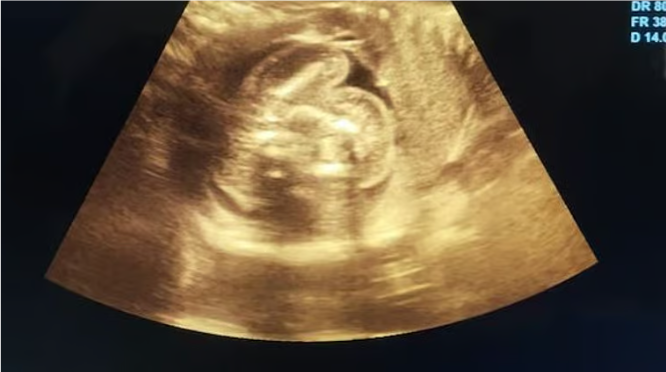

மகாராஷ்டிரத்தில் ஓர் கர்ப்பிணிப் பெண்ணிற்கு அரிய வகையான ‘கருவினுள் கரு’ எனும் நிலை உண்டாகியிருப்பதை கண்டுபிடித்த மருத்துவர்கள்! 🕑 Wed, 29 Jan 2025

மகாராஷ்டிரத்தில் ஓர் கர்ப்பிணிப் பெண்ணிற்கு அரிய வகையான ‘கருவினுள் கரு’ எனும் நிலை உண்டாகியிருப்பதை கண்டுபிடித்த மருத்துவர்கள்!

மகாராஷ்டிரத்தில் ஓர் கர்ப்பிணிப் பெண்ணிற்கு அரிய வகையான ‘கருவினுள் கரு’ எனும் நிலை உண்டாகியிருப்பதை மருத்துவர்கள் கண்டுபிடித்துள்ளனர்.